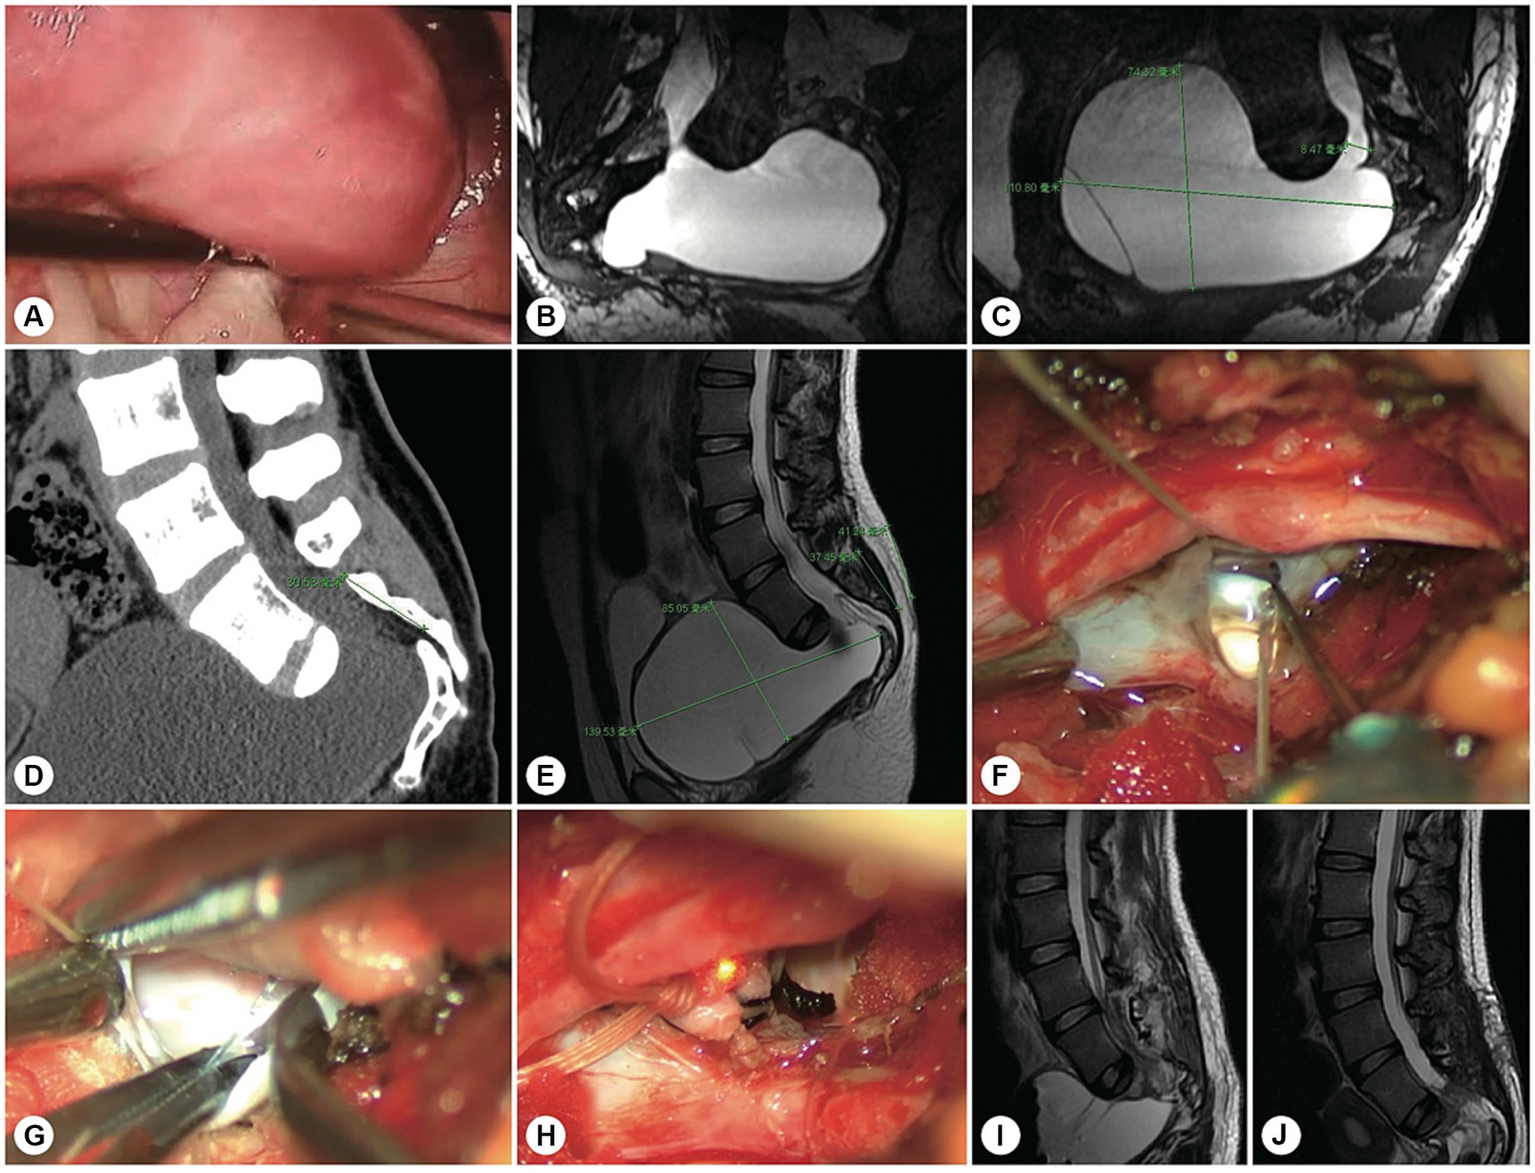

Figure 6

A representative patient with both sacroanterior and sacral cysts. A 22 years-old woman presenting with abdominal pain was found to have a pelvic mass. (A) Laparoscopic exploration revealed that the pelvic lesion was connected to the sacral canal. (B) Coronal MR image showing wide neck leakage between the end of the dural sac and the sacral canal. (C) Sagittal MR image revealing a giant sacroanterior cyst connected to a sacral cyst without nerve root fibres inside. (D) Sagittal CT image showing a sacroanterior bone defect. (E) A precise incision was made. (F) Intraoperatively, abundant cerebrospinal fluid leaked from the orificium, suggesting high intracystic pressure. (G) No spinal nerve root fibres were identified in the leakage orificium. (H) The leakage orificium was ligated. (I) On MRI, 1 week after the operation, the sacroanterior cyst had shrunk. (J) Three months after surgery, the sacroanterior cyst had almost completely disappeared on MRI.